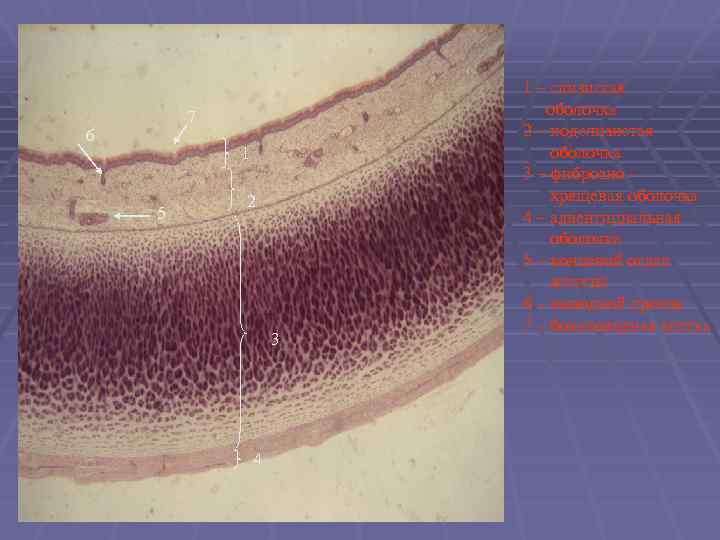

7 6 1 5 2 3 4 1 – слизистая оболочка 2 – подслизистая оболочка 3 – фиброзно хрящевая оболочка 4 – адвентициальная оболочка 5 – концевой отдел железы 6 – выводной проток 7 – бокаловидная клетка